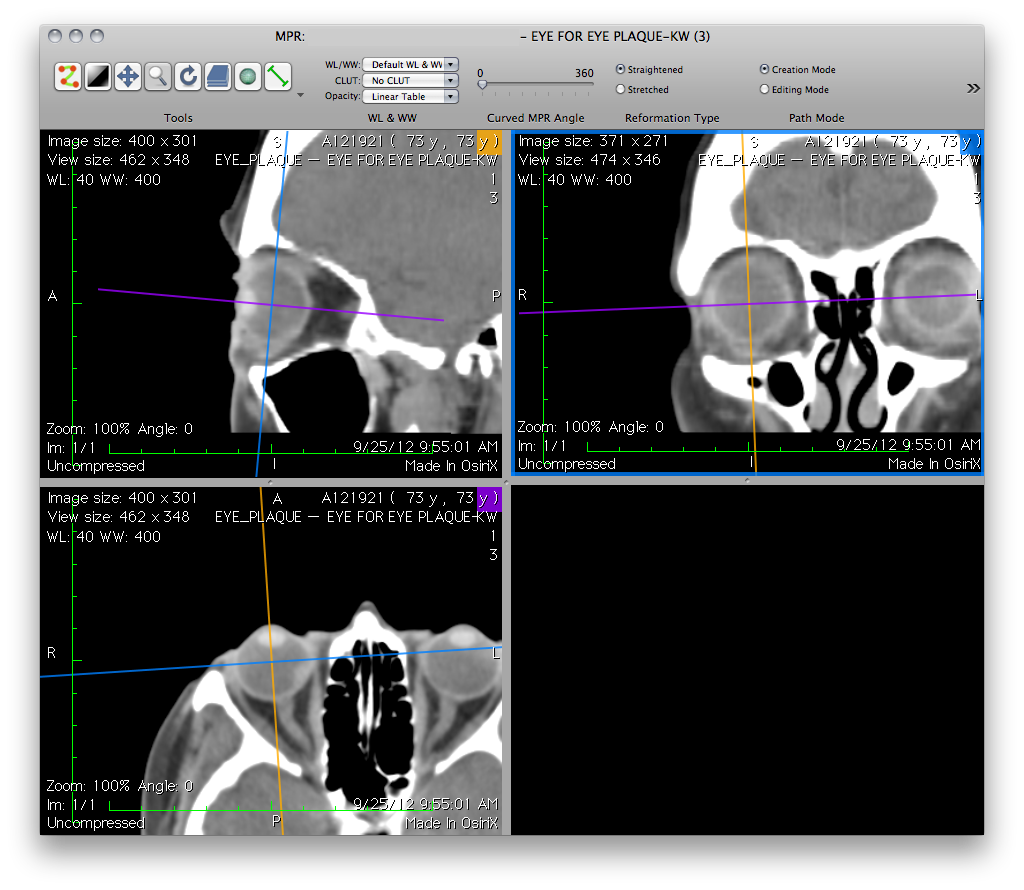

• Drag and rotate the axes until that the yellow axis marks the sagittal meridian (12 to 6 o'clock meridian on the retinal diagram) plane that bisects the eye, the blue axis marks the equatorial plane of the eye, and the purple axis marks the axial meridian plane that bisects the eye through the optic disc (3 to 9 o'clock meridian on the retinal diagram).

• In the axial image, the yellow axis is aligned with Plaque Simulator's X axis of the eye and passes through the apex of the cornea, the midpoint of the lens, and the posterior pole of the eye.

• Note that because the patient may not have been looking straight ahead during the scan, the axial, equatorial and sagittal reconstructions of the eye might not be parallel to the axial, coronal and sagittal planes of the body.

OsiriX: Preparing axial, equatorial and sagittal reconstructions for export to Plaque Simulator

• Magnify to taste.

Use the magnifier tool to adjust the CT image size so that the eye occupies a substantial portion of the pane, but is not obscured by text overlays.

• For best results with PS, the axial, coronal and sagittal reconstruction panes should be in the range 600 to 800 pixels wide.

OsiriXOrthogonalPlanes.png